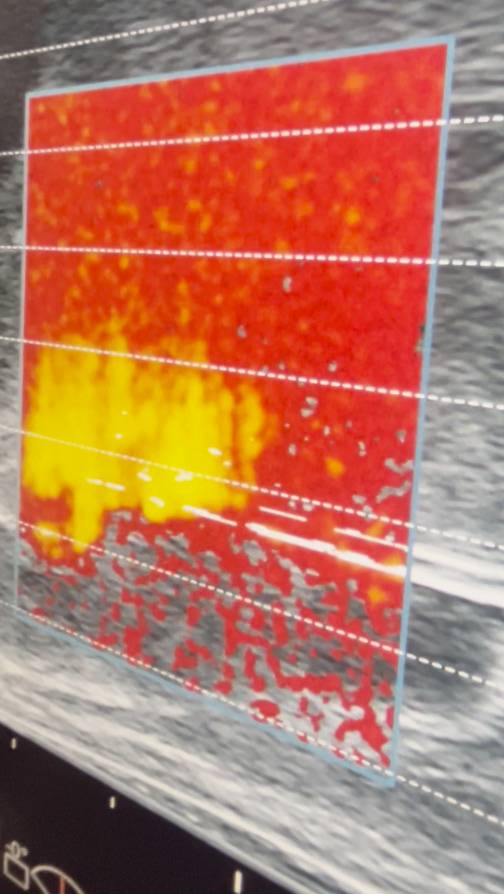

TMA wykorzystuje energię mikrofal, które podgrzewają tkankę do temperatury prowadzącej do nieodwracalnej denaturacji białek i martwicy komórek nowotworowych.